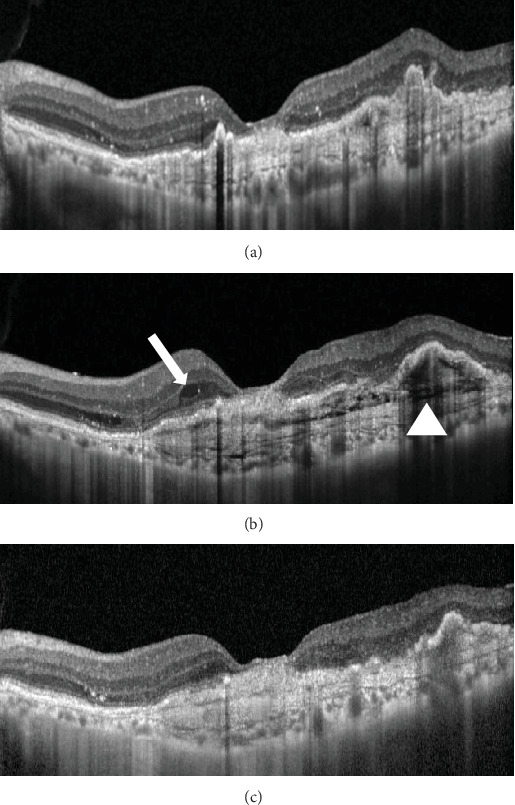

Purpose: The aim of this study is to report a unique case where brolucizumab administration resolved multilayered pigment epithelial detachment (MLPED) lamellae. Observations: An 80-year-old gentleman with polypoidal choroidal vasculopathy developed MLPED from long-term ranibizumab treatment. Switching to brolucizumab led to visual acuity improvement after three doses and complete resolution of fluid, reduced choroidal thickness, and MLPED collapse. Notably, the patient experienced a recurrence of MLPED, which again resolved after the fourth dose of brolucizumab. Conclusions and Importance: This case underscores the effectiveness of brolucizumab in resolving MLPED lamellae, a previously unreported phenomenon. Furthermore, it highlights the potential for visual acuity improvement despite MLPED resolution. Brolucizumab's mechanism of action, including its potent antivascular endothelial growth factor properties and enhanced tissue penetration, may contribute to the collapse of MLPED by modulating subretinal pigment epithelial fluid dynamics. Further research into molecular pathways, cellular interactions, and safety profiles is warranted to optimize the therapeutic role of brolucizumab.

Abstract Image